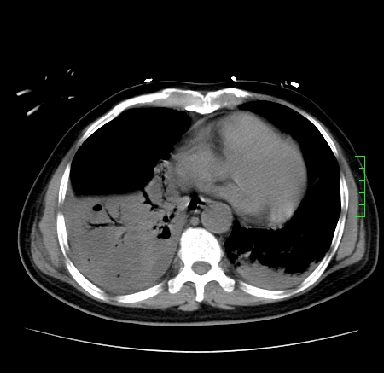

icu病人,几天都没明确诊断。m,76y,咳嗽、咳痰1周,伴气促,右胸痛入院,pe:t38.3c p135 r25 bp135/85。双肺可闻及大量湿罗音,心、腹未见明显异常。诊断:1心衰?2肺部感染?3冠心病?

双肺感染性病变,下叶膨胀不全,胸水,左室大。

1)两肺感染性病变(右肺下叶肺脓肿可能)。2)双侧胸腔积液,以右侧为甚。

ards,肺感染性病变,右下叶实变,双侧胸腔积液,右侧为著,叶间胸膜积液,右上肺陈旧性tb纤维灶,左室大。

考虑双肺感染、右肺下叶肺脓肿伴双侧胸腔积液,肺水肿。

考虑:双肺感染、右肺下叶肺脓肿,双侧胸腔积液,肺水肿.请结合临床.